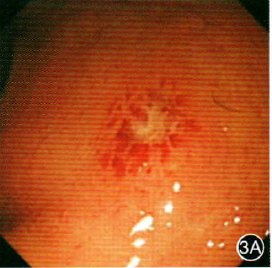

内镜下这些特征可能是艾滋病特征性表现